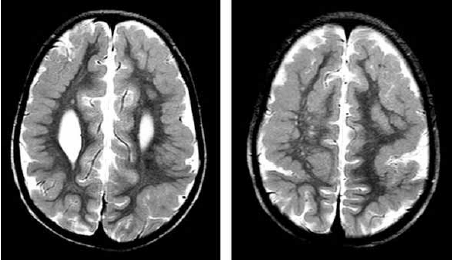

Paciente com atraso global do desenvolvimento e epilepsia. Na investigação foi realizada a ressonância magnética de crânio a seguir.

A achado de imagem sugere